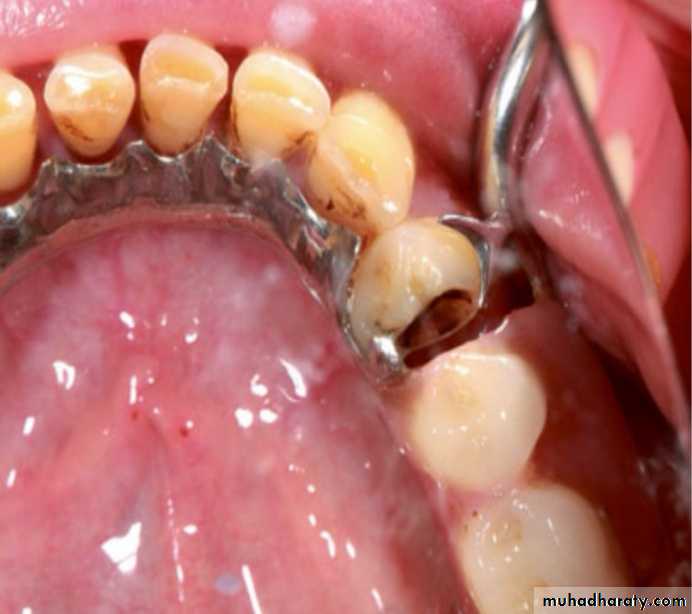

Clasps may not function properly in case of wear of the abutments due to caries, abrasion, or erosion on the facial or proximal surfaces or because of patient misuse.

However, it should be under-lined that these may be the reasons only if the RPD has been designed properly.

The design must have been completed using a surveyor for deciding the path of insertion and for tracing the survey line to obtain efficient retentive clasps.

If the function of the clasp decreases, it can be reactivated using pliers and bending the retentive arm into the undercut area

The clasp assemblies may lose their retentive

properties due to caries of the abutment teeth